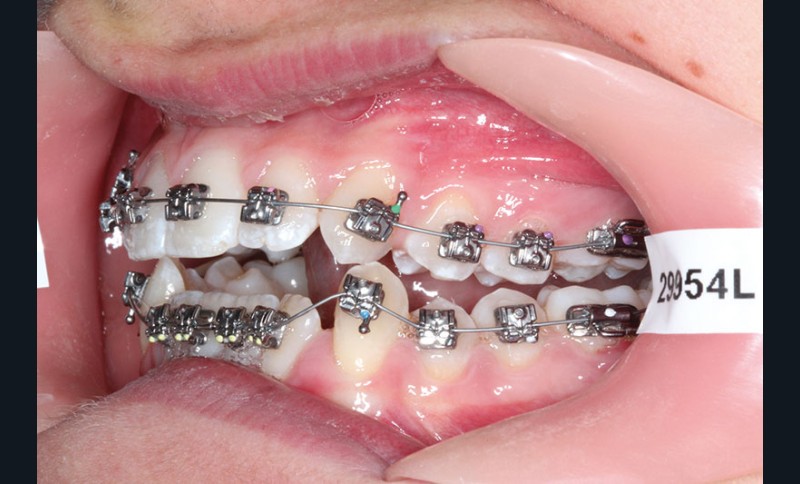

1re phase : recul des secteurs latéraux mandibulaires avec le Motion Classe III Carriere (fig. 4 à 6)

Nous mettons en place des bras latéraux Motion associés à des élastiques intermaxillaires ancrés sur des brackets sur 17 et 27 et une gouttière thermoformée maxillaire portée jour et nuit :

• 1er mois : élastiques 6 oz. 1/4”

• 2e mois et suivants : élastiques 6 oz.1/4“

L’objectif de cette étape est d’obtenir un recul des secteurs latéraux mandibulaires afin de positionner les molaires et canines en classe I et de réorienter le plan d’occlusion en haut en avant.